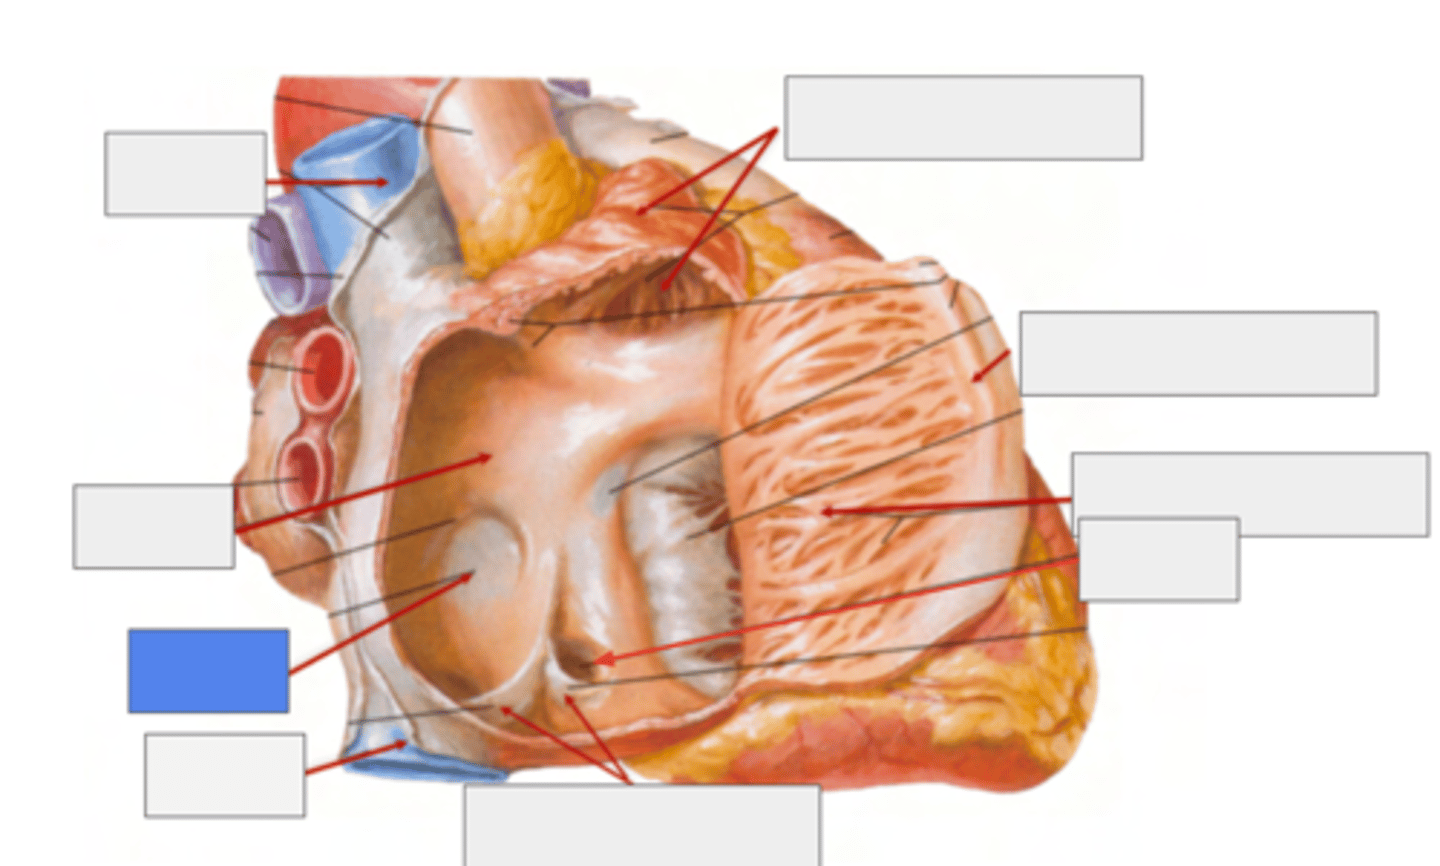

What is pointing the blue square?

valves of inferior vena cava and coronary sinus

What is the trabeculated wall in the atrium?

Right Auricle

What are the name of the musculi of the right auricle?

Musculi pectinati

TRABECULATED WALL VS THE SMOOTH INTERIOR PART OF THE ATRIA

What separates the trabeculated from the smooth walls in the atrium?

Crista terminallis